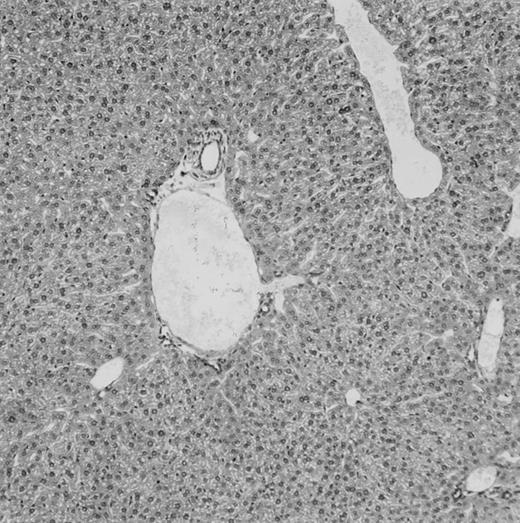

Histologic findings. Organs were collected at different times after BMT and tissue sections were stained with hematoxylin and eosin. Original magnifications for spleen (left) and liver (right) are ×40 and ×100, respectively. (A) B6 mice receiving FVB BM plus EpTK T cells. (B) Control group receiving BM only.

(C) B6 mice receiving FVB BM plus EpΔTK T cells and treated with GCV. (D) B6 mice receiving FVB BM plus EpΔTK T cells, treated with GCV, and developing a late onset GVHD (day 54).

Using this delivery mode, we observed that mice receiving a 7-day GCV treatment initiated at the time of transplantation were protected from GVHD. At day 60, the survival rate was 100% in the GCV-treated group receiving EpTK CD3+ T cells, and was still 92% at the end of a 120 day follow-up (Fig 2A). Protected mice were apparently healthy, presented no visible skin lesions, and gained weight comparably to controls receiving only BM (data not shown). Hematologic reconstitution was analyzed by flow cytometry at different times from day 14 to day 212. Splenocytes of GCV-treated animals were of donor H-2q origin in the B-cell (B220+) and non–B-cell (B220−) compartments, the latter containing donor Thy1.1+ T cells but no recipient Thy1.2+ T cells (Fig 3B). Finally, histological analysis in these animals showed nodular architecture in the spleen and no significant hepatocyte necrosis or portal mononuclear cell infiltrates in the liver (not shown) and similar to control animals receiving only BM. Taken together, these data indicate that a GCV treatment, administered at the onset of allogeneic BMT and with a course as short as 7 days, abrogates GVHD and allows a full recovery from the lethal irradiation.

Protection from GVHD was slightly less efficient in the group receiving EpΔTK CD3+ T cells. The survival rate was 79% at day 60 and 67% at day 120 (Fig 2B). However, two different outcomes must be distinguished. On the one hand, a majority of mice behaved as GCV-treated animals receiving EpTK T cells. They were apparently healthy, presented no skin lesions during a 120-day observation period, and showed complete donor-type hematologic reconstitution. There were no histological signs of GVHD in the spleen or liver (Fig 4C).